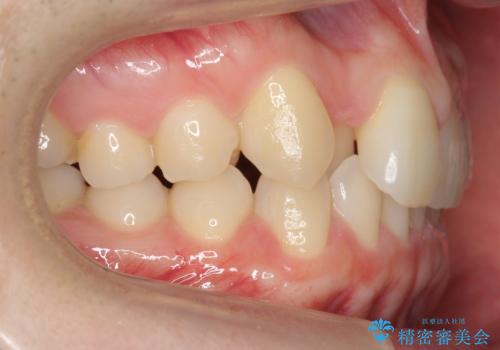

- 右上の前歯が内側に入っているのを気にして来院。

前歯が内側に入っていると、笑った時にそこが黒くなり、歯が抜けたように見えます。